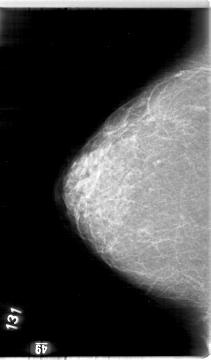

D_4004_1.RIGHT_CC

RIGHT_CC LINES 5386 PIXELS_PER_LINE 3151 BITS_PER_PIXEL 12 RESOLUTION 43.5 NON_OVERLAY